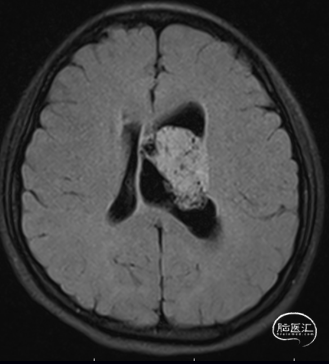

现病史:患者1年前无诱因出现间断头痛,不伴随恶心呕吐等,起初未在意。1个月前上述症状加重,伴随恶心,在当地医院检查CT发现左侧脑室内占位病变,左侧脑室扩大。家人为求彻底治疗来我院,门诊以“1. 左侧脑室内占位;2. 左侧脑室积水”为诊断收入我科。

FLAIR

头部磁共振提示:左侧侧脑占位病变,增强后不染色